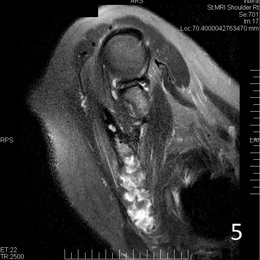

An example of a Fibrous Dysplasia MRI is shown.